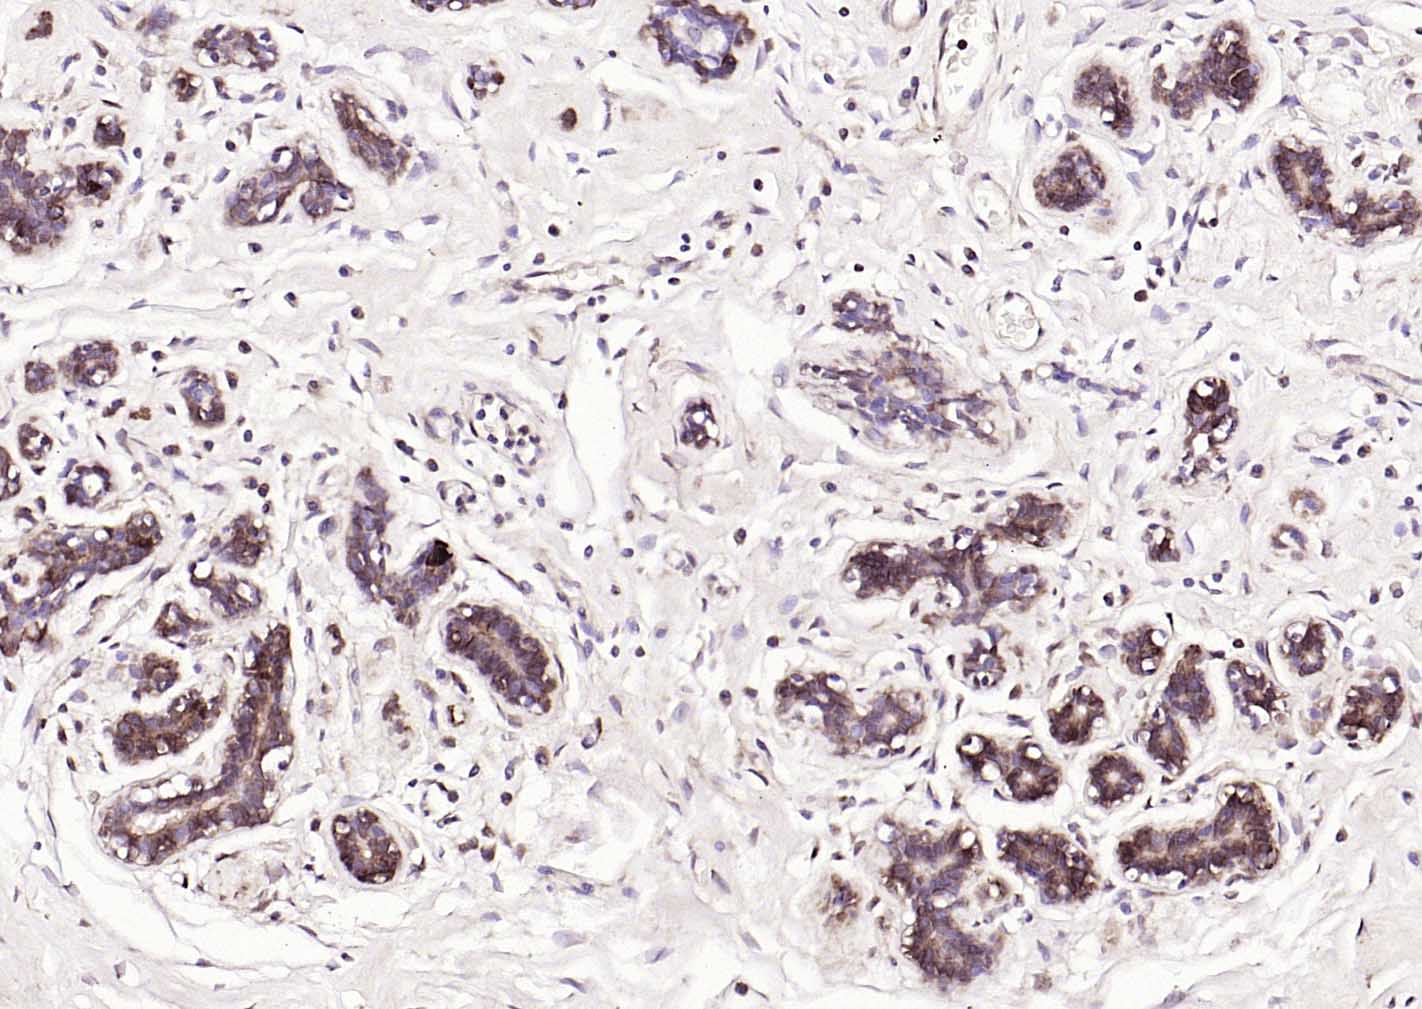

Paraformaldehyde-fixed, paraffin embedded (human breast); Antigen retrieval by boiling in sodium citrate buffer (pH6.0) for 15min; Block endogenous peroxidase by 3% hydrogen peroxide for 20 minutes; Blocking buffer (normal goat serum) at 37°C for 30min; Incubation with (S100A1 ) Polyclonal Antibody, Unconjugated (bs-41209R) at 1:200 overnight at 4°C, followed by operating according to SP Kit(Rabbit) (sp-0023) instructionsand DAB staining.